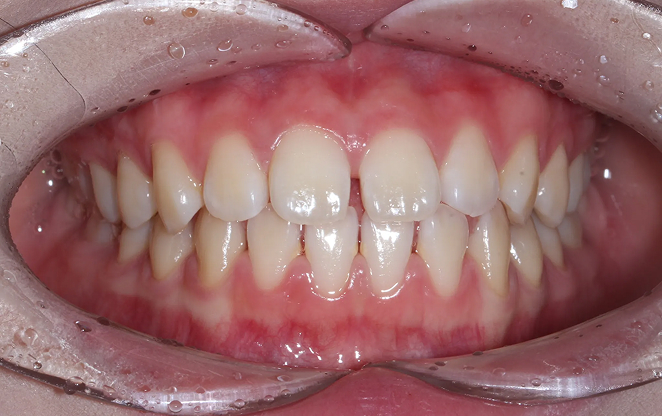

Before

After